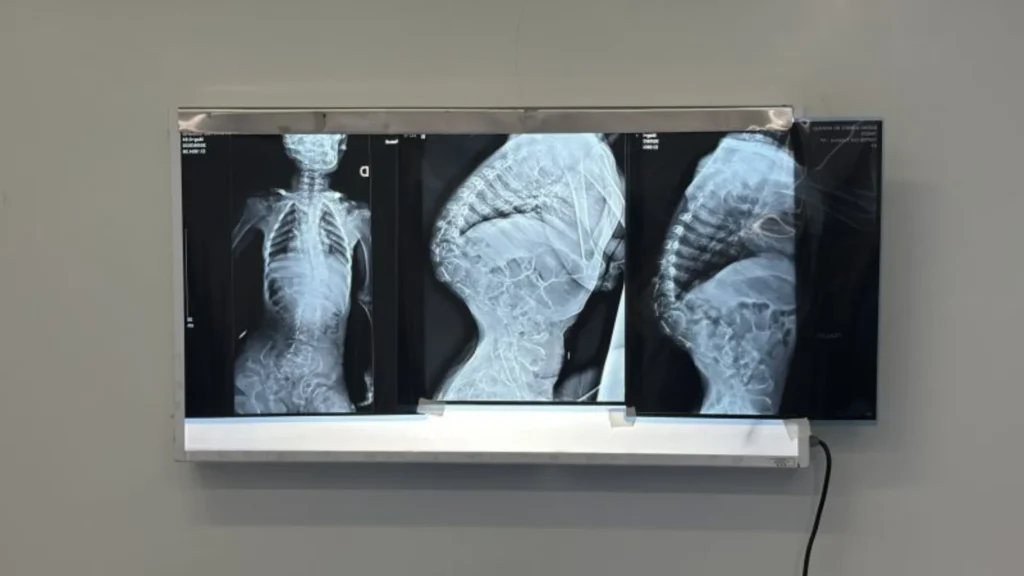

Cirurgia inédita realizada em SC pode fazer criança paraplégica andar

Uma cirurgia inédita realizada no Hospital Infantil Joana de Gusmão (HIJG), em Florianópolis, trouxe uma nova esperança de recuperação para uma criança de 9 anos diagnosticada com paraplegia. O procedimento, de alta complexidade e nunca antes executado na unidade, utilizou tecnologia avançada e abre a possibilidade de retomada dos movimentos dos membros inferiores.

A intervenção foi conduzida por uma equipe multidisciplinar e contou com o uso de neuronavegação — tecnologia comparada a um GPS cirúrgico — aliada à modelagem tridimensional da coluna vertebral. A aplicação conjunta dessas ferramentas permitiu maior precisão, redução de riscos e melhor planejamento, em uma cirurgia realizada em duas etapas.

A criança é portadora de uma displasia esquelética rara, enfermidade que causa deformidades severas na coluna vertebral e pode comprometer funções neurológicas e respiratórias. Sem acesso a tratamento especializado nos primeiros anos de vida, a condição evoluiu para compressão da medula espinhal em diversos níveis, resultando em paraplegia, perda de sensibilidade nos membros inferiores e dificuldades respiratórias e alimentares.